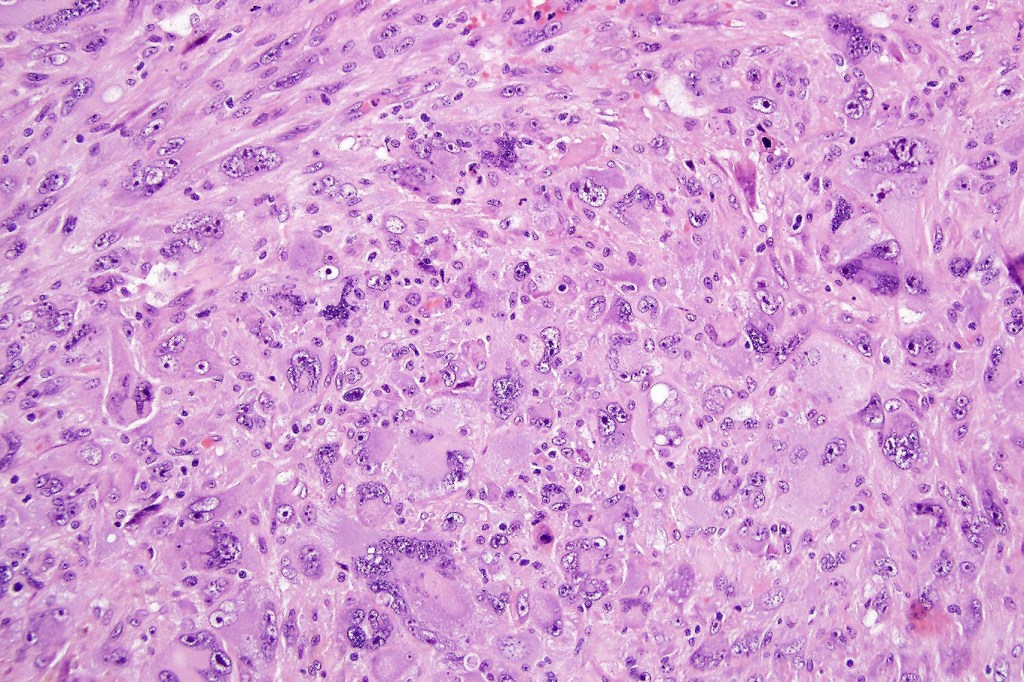

•Biphasic tumor

•Possible epithelial to mesenchymal transition

•Admixture of squamous carcinoma & pleomorphic spindled cell, osteoid, chondroid, MFH-like +/- osteoclast-like giant cells & rarely, smooth muscle, skeletal muscle, myofibroblastic or angiosarcomatous elements